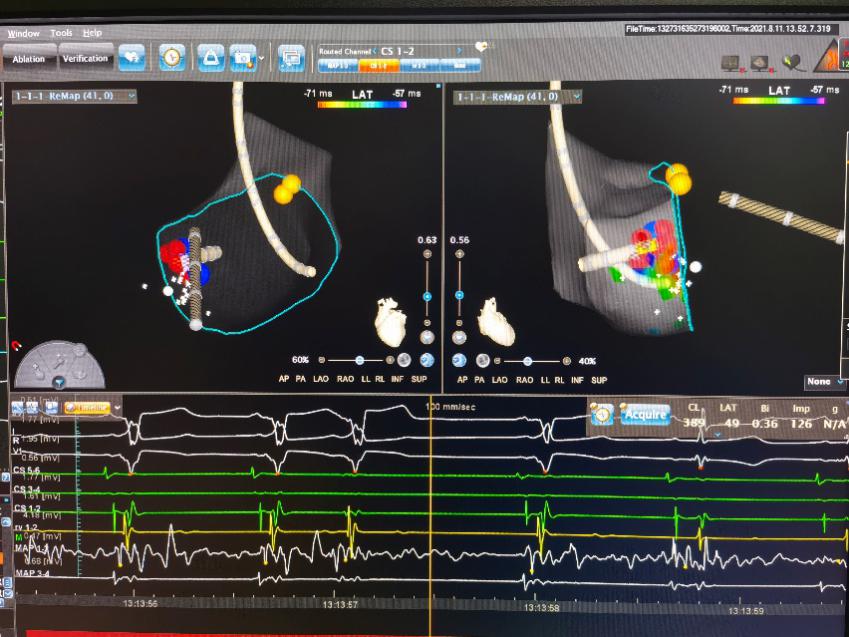

三维标测下的放电消融,旁道迅速被阻断。

1周前恬恬再次发病,家属再次联系捷克论坛 ,坚决要求手术治疗。由于孩子年龄小、风险大,儿童心血管副主任医师刘丽萍、袁勇华、刘震宇和成人心内科副主任医师张良对恬恬的病情进行全面评估及讨论,制定了严密的手术方案。8月11日,医疗团队为恬恬实施手术,术中通过电生理检查确定恬恬为“房室折返性心动过速”,在三维标测下找到靶点,并成功消融,术中几乎无出血,辐射量极少。术后恬恬迅速恢复,在术后第三天就顺利出院了,家长十分感激。

刘丽萍主任介绍,阵发性室上性心动过速(paroxysmal supraventricular tachycardia, PSVT)是儿童就医的最常见心律失常之一,有研究显示儿童PSVT的发病率为1/1 000~1/250,PSVT得不到及时终止或者反复发作,可能导致心力衰竭和晕厥发生,甚至有猝死风险,部分预激综合征还可以导致预激性心肌病,严重影响儿童的日常生活、运动和学习。经导管射频消融是目前根治室上性心动过速的唯一手段。 恬恬的心电图类型属于预激综合征,这是儿童中最常见的一种室上性心动过速,药物控制只能减少发作,不能根治。据统计,该手术的成功率可达90%以上。儿童射频消融手术由于难度大,很多医疗机构未开展此项技术。恬恬是儿童心血管专科完成手术的最小年龄的患者,团队利用“绿色”三维标测技术,手术成功率明显提高,而且辐射量少,对儿童来说安全有效,且更有利于维护儿童的健康。